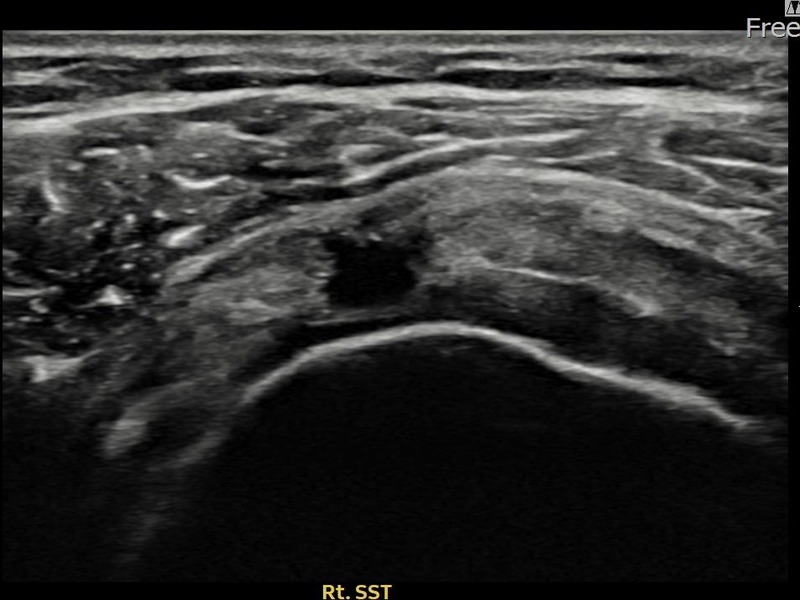

최ㅇㅇ님 · 우측 극상근건 관절면측 파열 진행형

우측 어깨 파열이 진행된 상태로 수술 없이 치료를 원해 내원하셨습니다. 다각도 초음파 평가 후 축소봉합술을 시행하여 힘줄 구조가 안정화되었습니다.

상세 보기 →